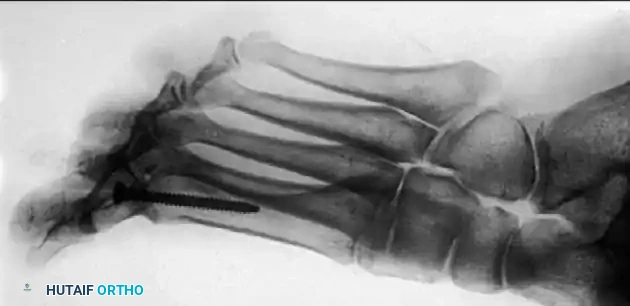

Modern fixation techniques have revolutionized fusion rates, achieving successful arthrodesis in 94% to 98% of cases. Politi et al. conducted a comprehensive biomechanical study demonstrating that the most stable fixation construct is a combination of an interfragmentary oblique lag screw and a dorsal neutralization plate.

Associated Surgical & Radiographic Imaging